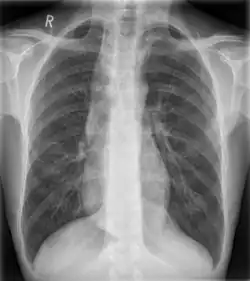

| Widened mediastinum | |

|---|---|

| Other names | Mediastinal widening |

![]() | |

| Widened mediastinum in a patient with achalasia | |

Widened mediastinum/mediastinal widening is where the mediastinum has a width greater than 6 cm on an upright PA chest X-ray or 8 cm on supine AP chest film.[11]

A widened mediastinum can be indicative of several pathologies:[12][13]

- aortic aneurysm[14]

- aortic dissection[15]

- aortic unfolding

- aortic rupture

- hilar lymphadenopathy

- anthrax inhalation - a widened mediastinum was found in 7 of the first 10 victims infected by anthrax (Bacillus anthracis) in 2001.[16]

- esophageal rupture - presents usually with pneumomediastinum and pleural effusion. It is diagnosed with water-soluble swallowed contrast.

- mediastinal mass

- mediastinitis

- cardiac tamponade[17]

- pericardial effusion

- thoracic vertebrae fractures in trauma patients.